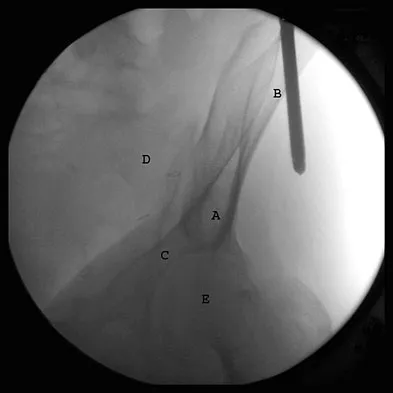

The correct starting point for an external fixation half pin placed into the anterior inferior iliac spine (AIIS) is labeled by what letter in Figure 3?

Explanation